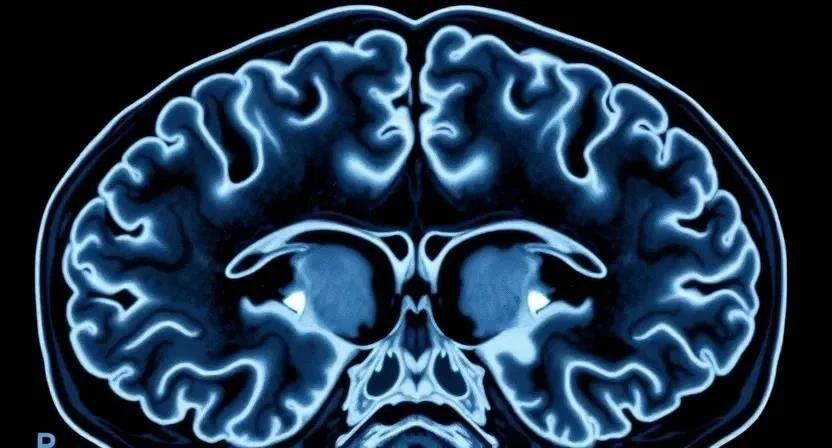

Диагностика эпилепсии – это сложный процесс, требующий комплексного подхода. Основным методом является электроэнцефалография (ЭЭГ), которая регистрирует электрическую активность мозга. ЭЭГ-мониторинг с видеозаписью позволяет наблюдать за приступами и сопоставлять их с изменениями на ЭЭГ. Магнитно-резонансная томография (МРТ) и компьютерная томография (КТ) помогают выявить структурные изменения в мозге. Лабораторные исследования, такие как анализ крови и мочи, могут исключить другие причины приступов. Консультация невролога – обязательный этап диагностики. Мне пришлось пройти все эти обследования, чтобы подтвердить диагноз у моего племянника.